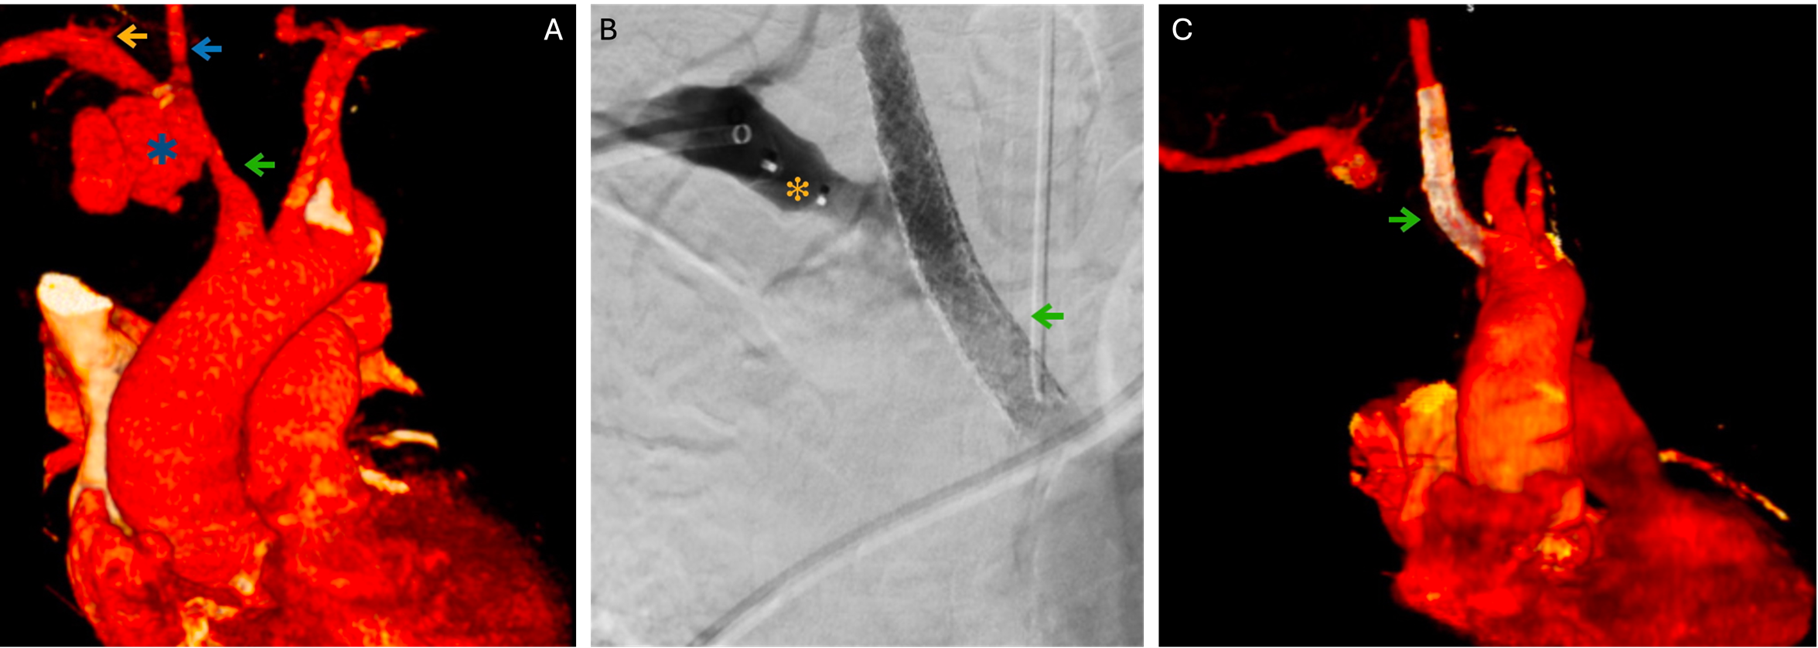

Aortic Trauma: A Rare Case Report

Carolina Lacerda Rodrigues, Giovanna Jurucunas de Oliveira Gaeta, Jacqueline Mendes da Cruz, Felipe Ramon Menezes da Silva, Thauane Pereira Nunes, Pedro Gomes Santana, Ana Paula de Carvalho Miranda Rosati, Luis Fernando Rosati

bjcr35